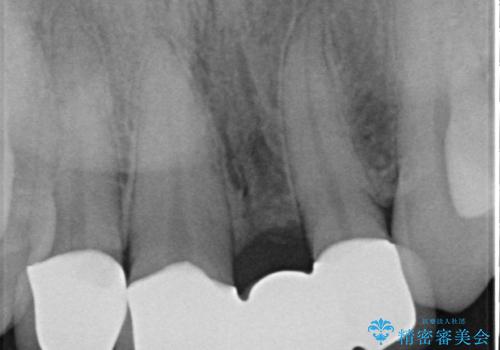

- 前歯の歯並びや色が気になるといらっしゃった方の症例です。

前歯4本をオールセラミッククラウンで補綴することで、歯の並びや色の改善を行いました。